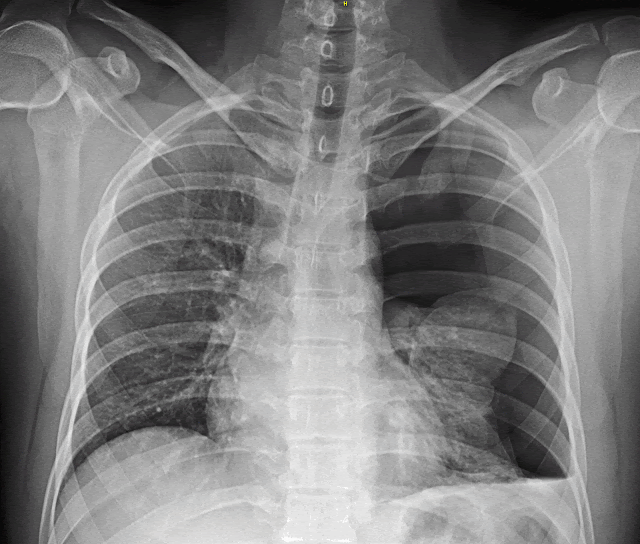

Le pneumothorax peut être spontané (son origine est alors inconnue), traumatique ou secondaire à une maladie pulmonaire.

Le pneumothorax désigne un échappement d'air du poumon qui va entre le poumon et la paroi thoracique dans la plèvre (organe qui recouvre le poumon et l'intérieur de la cavité thoracique).

Il se traduit par un décollement de la plèvre et une compression du poumon entraînant des douleurs et des difficultés à respirer.

En cas de pneumothorax, une sorte de poche d'air se forme entre le poumon et la plèvre, laquelle fait pression sur les poumons.